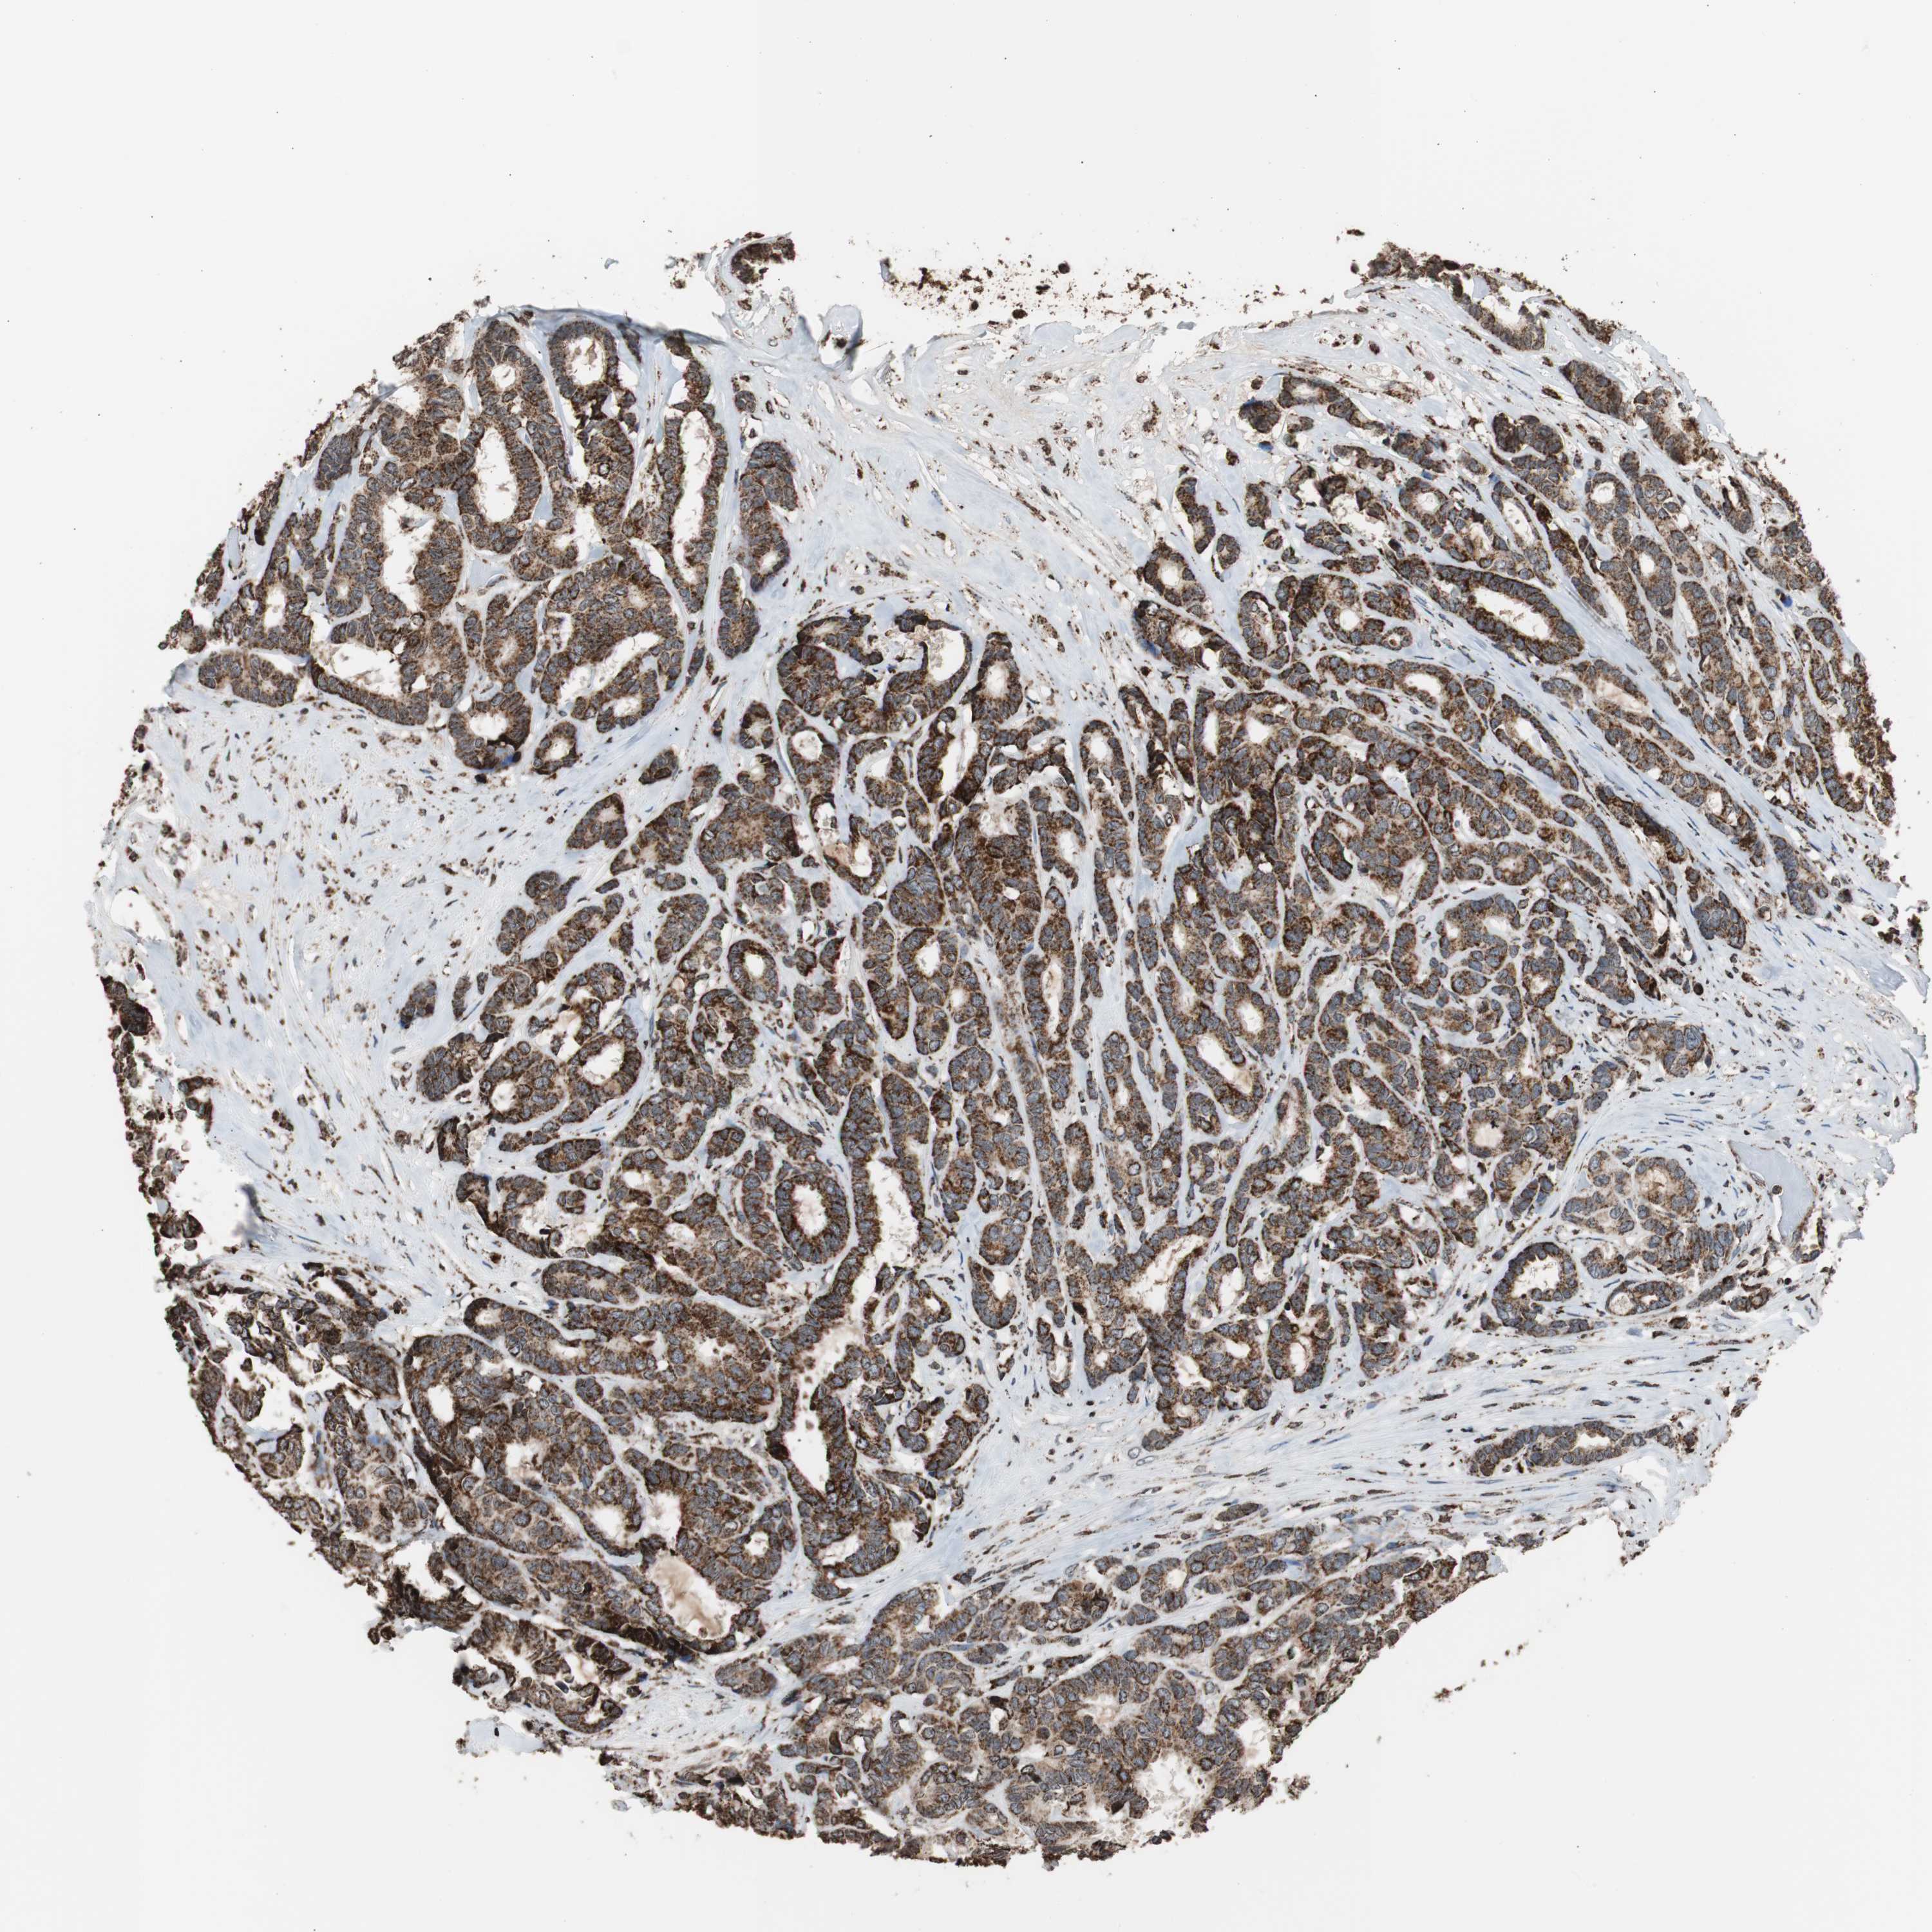

CANCER BREAST CANCER Show tissue menu

BRCA TCGA BRCA VALIDATION PROTEIN EXPRESSION